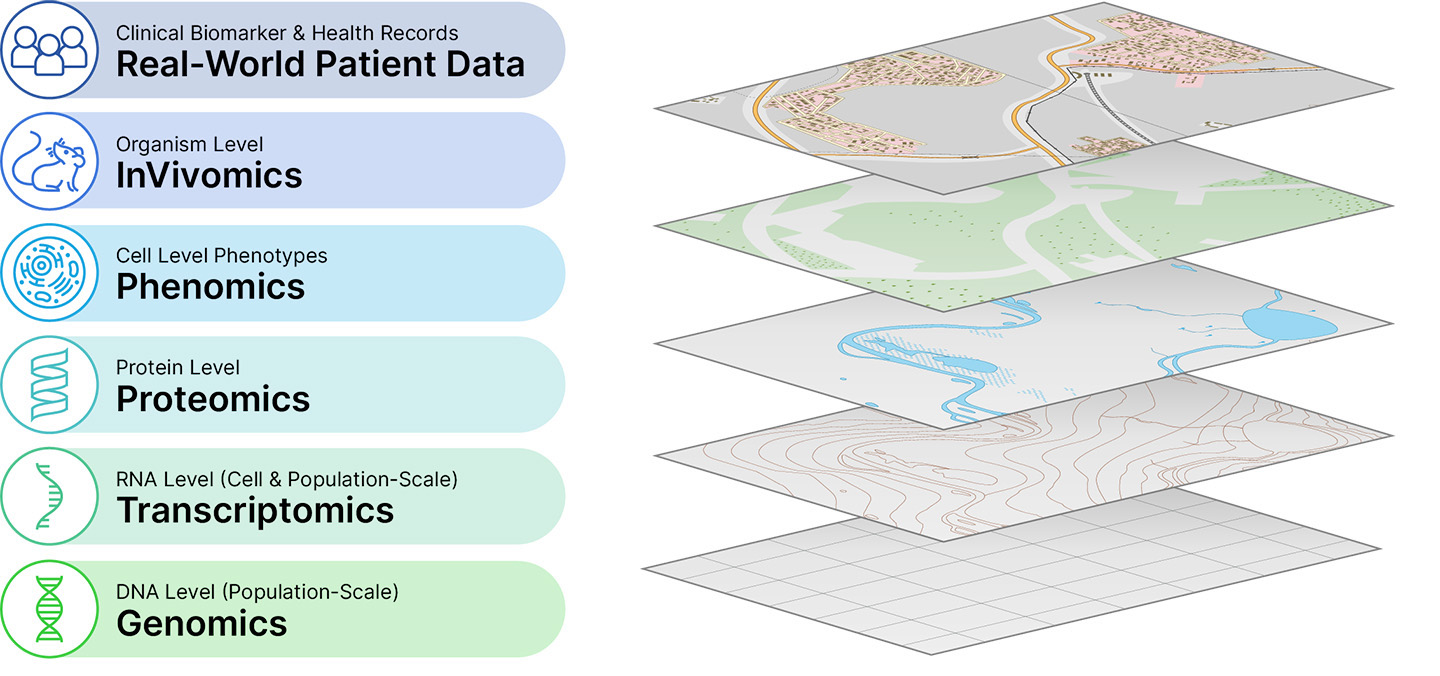

Recursion is a leading clinical stage TechBio company decoding biology to industrialize drug discovery. Central to our mission is the Recursion Operating System (OS), a platform built across diverse technologies that enables us to map and navigate trillions of biological, chemical, and patient-centric relationships across over 50 petabytes of proprietary data. We frame this integration of the physical and digital components as iterative loops, where scaled ‘wet-lab’ biology, chemistry, and patient-centric experimental data are organized by ‘dry-lab’ computational tools in order to identify, validate, and translate therapeutic insights. We believe Recursion’s unbiased, data-driven approach to understanding biology will bring more, new, and better medicines at higher scale and lower cost to patients.

Figure 1. A simple formula is used across technology industries to map and navigate complex systems. First, high-dimensional data is generated, aggregated and organized to create digital representations. Then, AI/ML algorithms make predictions about that system that can be tested in reality. The result is a virtuous cycle of learning and iteration.

At Recursion, we are pioneering the integration of innovations across biology, chemistry, automation, data science and engineering to industrialize drug discovery in a full-stack solution across dozens of key workflows and processes critical in discovering and developing a drug. For example, by combining advances in high content microscopy with arrayed CRISPR genome editing techniques, we can rigorously profile massive, high-dimensional biological and chemical perturbation libraries in multiple human cellular contexts to create digital ‘maps’ of human biology. Leveraging advances in scaled computation, we can conduct massive virtual screens to predict the protein targets for billions of chemical compounds. Similarly, data generated from our automated DMPK module and InVivomics platform enables us to predict ADME properties and identify toxicity signals, respectively, significantly faster than traditional methods. We believe that by harnessing advances in technology to industrialize drug discovery, we can derive novel biological insights not previously described by scientific researchers, reduce the effects of human bias inherent in discovery biology and reduce translational risk at the program outset.

| “From our perspective there are two key drivers that will determine the winners in this race: data and execution.” | | The Differentiator Will Be Data and Execution Extending our view out beyond the near term and over the next decade, it feels possible, and even probable, that there will be a small number of very powerful companies in TechBio who may supplant much of what we call BioTech today. Who will these companies be and how will they win? While compute is supply-constrained right now, it has also never been anywhere near as abundant as it is today. Table-stakes in this race over the next few years will be access to dedicated compute and robust ML/AI and software engineering teams. That is why Recursion has continued investing in BioHive-1, our on-premise supercomputer. We announced in late 2023 an expansion of the computer with our partners at NVIDIA that is likely to make it the fastest supercomputer wholly owned and operated by any biopharma company on Earth, including all the big ones. We also have an incredible, talented and growing team of ML researchers and engineers working to leverage this compute to advance the OS. We’ve grown both organically on these teams and by acquisition when needed. But as I said, these are table stakes. From our perspective there are two key drivers that will determine the winners in this race: data and execution. There is a divergence of opinions on what sort of data to use. There are those who believe that much of the data needed to solve the biggest problems in drug discovery and development exist today, either publicly or in the hands of large pharmaceutical companies. There is some evidence to support this idea; for example, the incredible progress in protein folding has been driven by sophisticated compute applied to the Protein Data Bank (PDB), a publicly available dataset. But there are few other examples in our field of data as robustly and carefully annotated as in the PDB. In fact, it is well-understood that the majority of data in the published literature cannot be recapitulated by other laboratories. Turning to large pharmaceutical companies, who obviously have large quantities of data from their longstanding operations in drug discovery and development, we find more headwinds. First, few if any of these large datasets were built for the purpose of machine-learning. And while that doesn’t mean machine learning and AI cannot be a useful tool, the unimodal nature of the data in these sources and the lack of inter-experiment controls, especially from preclinical and clinical sides, will make it challenging to extract enough value. Further, the success of large language models trained across the internet and the subsequent lawsuits we are beginning to see from content purveyors whose data was used to train these models (e.g., https://www.nytimes.com/2023/12/27/business/media/new-york-times-open-ai-microsoft-lawsuit.html) should be making it clear to large pharma companies that they must be cautious about sharing these data. For all of the reasons above, at Recursion we have always believed that generating and aggregating large-scale, iterative many-modal data will be the fastest path to achieving our mission to decode biology. We have now done more than 200 million experiments across multiple -omics modalities. We have also signed our first data aggregation partnership with Tempus, where we now have access to the DNA and RNA-sequencing data of over 100K oncology patients on which we can train causal-AI models. And while each layer of our data is powerful, the true magic is found when we combine them together to train more general models of biology spanning massive cellular -omics data, animal omics data and human patient omics data. We believe this deeply enough that you can expect us to continue investing deeply in building data across new layers and partnering to aggregate the proprietary datasets we believe are key to our long-term ambition. |